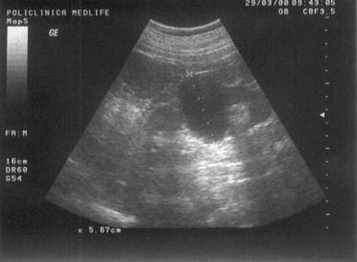

Figura 1. Vezica urinara

Figura 2. Chist renal stang situat in treimea medie

Figura 3. Chist ovar drept

Figura 4. Chist hepatic